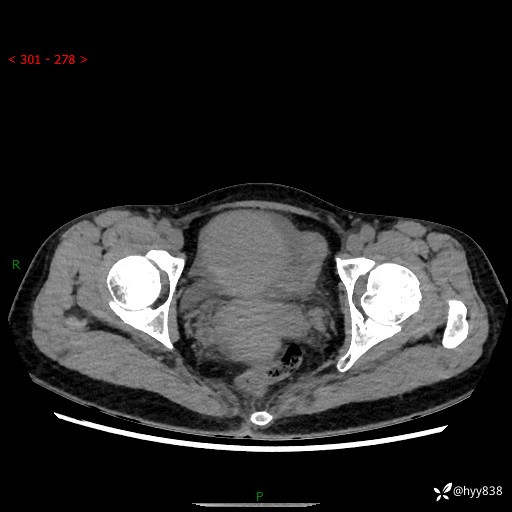

【患者信息】:女,50岁

【主诉】:外院超声发现腹盆肿块,为进一步诊治来我院,门诊已“盆腔肿块”收入院。

腹盆CT平扫+增强

【临床诊断】:盆腔肿瘤